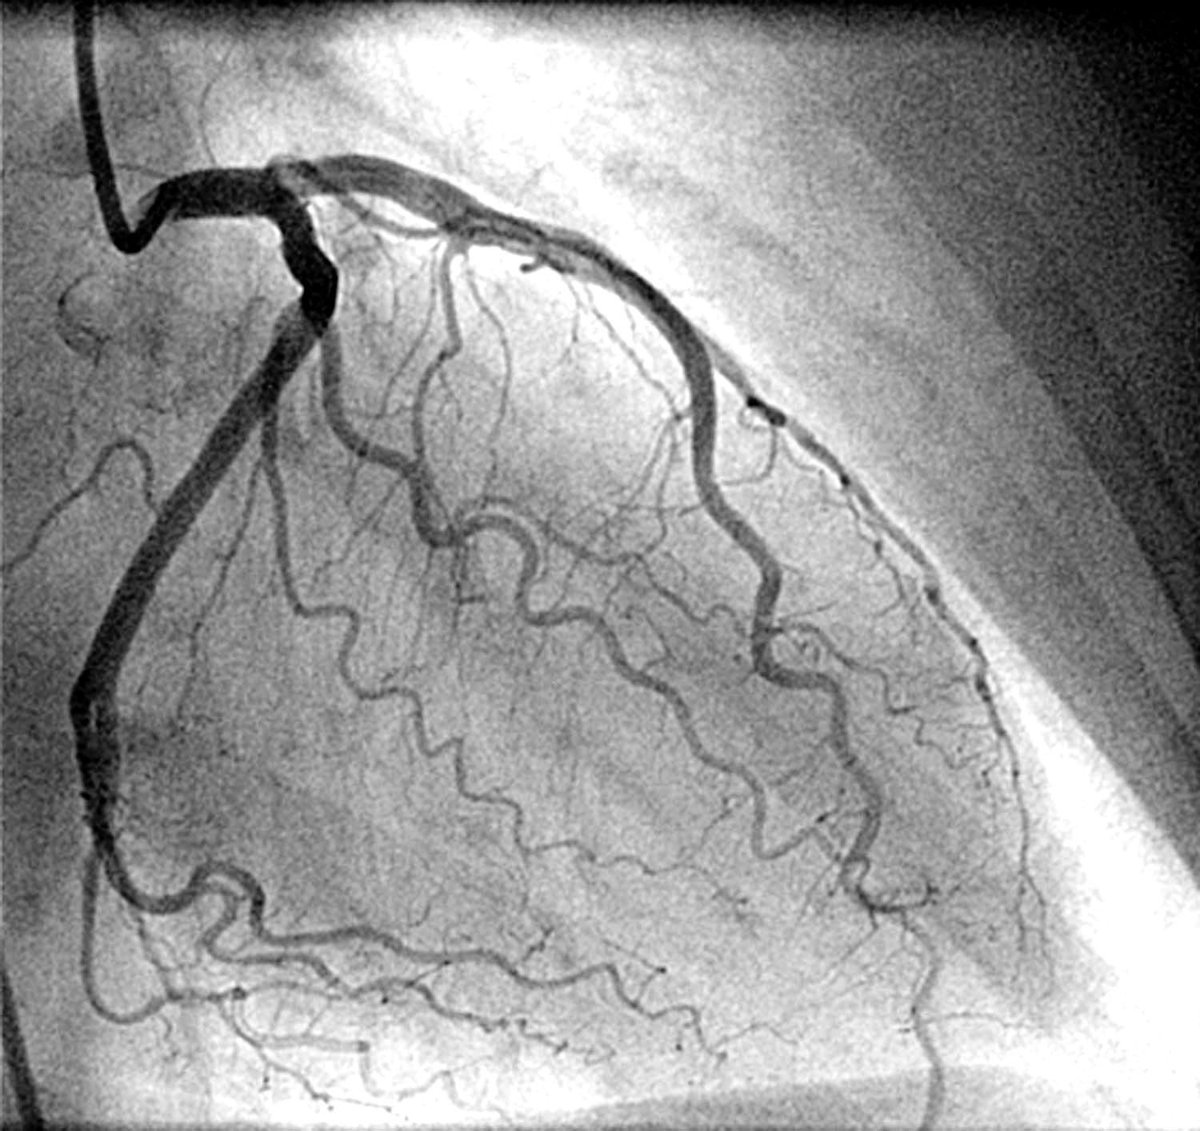

بالنسبة لقسطرة القلب .. الأمر يختلف

تأثر الكلى يعتمد على وضع المريض اثناء التعرض للصبغة

اذا كان مستقر والقسطرة غير طارئة فالأمر اقرب الى ما سبق ذكره .. وإذا كان غير مستقر فالخطر اعلى (توجد بعض الوسائل التي تساعد على حساب الخطر)

يجب التذكير ان قسطرة القلب قد تكون منقذة للحياة!